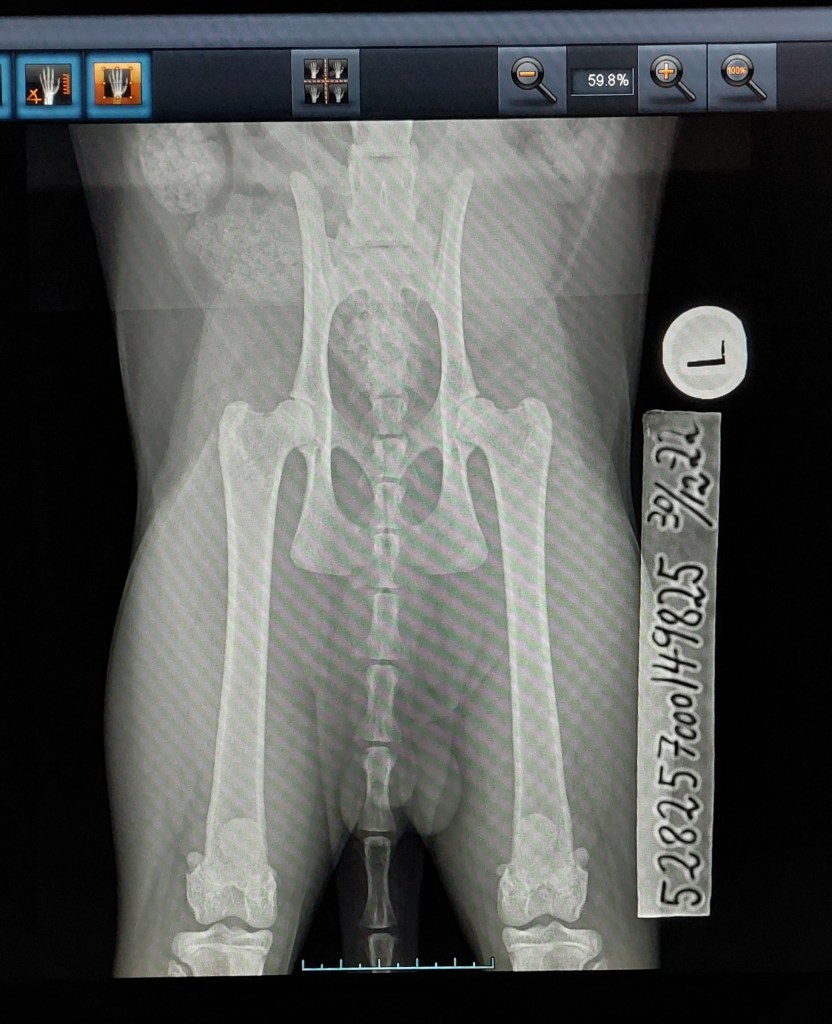

Along with Nylah I brought Rigo to his hip x-ray. I think his hips looks rather promising, so I dare to hope for normal hips – fingers and toes crossed ❤ His pictures has also been sent to PawPeds. – Rigo had to retake his pictures due to wrong ID-tape.

Results below.

The results weren’t what I hoped for, but still something I can work with. His results from PawPeds were mild dysplasia grade 1-1. I still want to compare results with OFA, so the pictures will be sent there for a second evaluation.